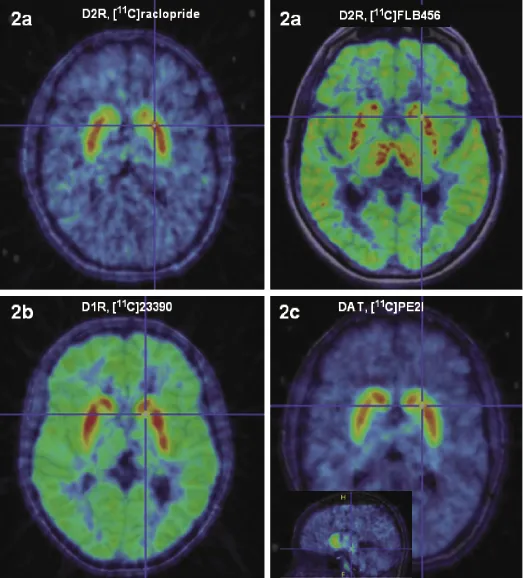

The precise anatomical location of the dopamine receptors in the human brain has been most fully established for the dopamine D2 receptors. In the adult human brain, D2R mRNA is markedly expressed in the striatum, neocortex, hippocampus, and amygdaloid complex, and differential expression is found in the thalamus as well as in most of the hypothalamic nuclei [15, 16]. D2R expression also follows a regional density pattern; there is a density gradient of D2R in decreasing order from the striatal structures, to the thalamus, to the midbrain, and finally, to the neocortex [17–19]. The dopamine D2R distribution in the neocortex is low, uneven, and varies between higher values in the temporal lobes (including hippocampus and amygdala) to minute receptor densities in the occipital lobes [20, 21]. Very heterogeneous D2R density is also found in the thalamus and in the striatum [22]. (Fig. 1.2a shows D2/D3R distribution as measured by molecular imaging in humans in vivo)

FIGURE 1.2 Dopamine receptor (D1, D2, D3) and dopamine transporter distribution throughout the brain as measured by in vivo molecular imaging in humans by PET. (a) Regional radioactivity of [11C]raclopride, representing binding to the striatal D2/D3DRs, and [11C]FLB 456, representing binding to the extrastriatal D2/D3DRs. (b) Regional radioactivity of [11C]SCH23390, representing binding to the D1/D5DRs. (c) Regional radioactivity of [11C]PE2I, representing binding to the DAT. Summation PET images at transaxial and saggital planes. Substantia nigra indicated in saggital plane.

The cells expressing D1R mRNA are localized in the striatum, cerebral cortex, and bed nucleus of stria terminalis [16]. Dopamine D1R mRNA expression in the human cerebral cortex is the most abundant of all dopamine receptors. It is distributed in a laminar pattern and differs quantitatively between the cortical regions and subregions, with the highest expression in the medial orbital, insular, and parietal cortices [27]. Extremely low levels of D1R mRNA are found in the hippocampus, diencephalon, brainstem, and cerebellum, suggesting that neurons in those areas can mediate dopamine transmission via D1R, although mainly it would be mediated via D2/D3Rs. In the normal adult human brain, D1Rs show a widespread neocortical distribution, with D1R predominantly localized on spines and shafts of projection neurons [28]. D1Rs are found in high density in the basal ganglia, including regions of the caudate, putamen, globus pallidus, and SN [18, 29]. (D1R binding distribution in vivo is depicted in Fig. 1.2b). D1Rs in the globus pallidus and the SN are most likely localized on terminals, as there are no D1R mRNA expresssing cells in those regions. Within the basal ganglia, D1Rs are most abundant on GABAergic neurons expressing dynorphin/substance P [30].